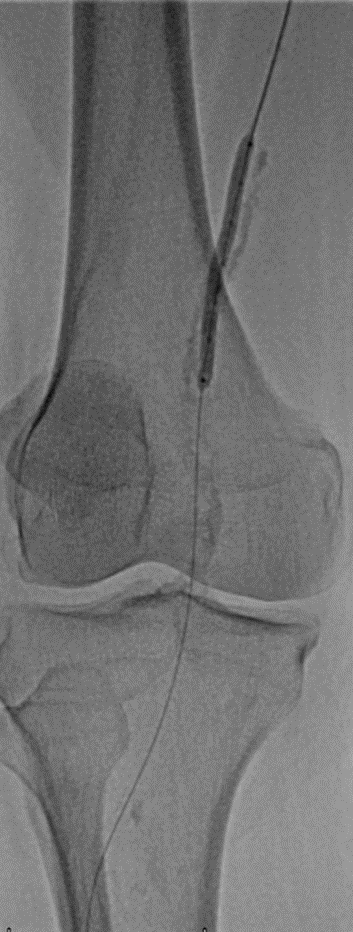

术中,团队首先使用开通导丝突破重度钙化病变,然后用2.0、2.5、3.0*150mm普通球囊逐级预扩张。造影显示血流较前稍改善,但钙化病变处仍有严重残余狭窄。

随后使用LiqMagic?P18外周血管内冲击波导管进行钙化斑块的压裂。根据血管尺寸,团队选择了4.0*60mm和5.0*60mm两个规格在4atm压力下逐段扩张整段病变,共进行了6个周期的冲击波治疗,将冲击波球囊加压至12atm显示病变狭窄解除,均匀扩开,保压1min后造影结果显示血流恢复通畅,钙化部位的残余狭窄明显改善。

▲4*60冲击波球囊扩张